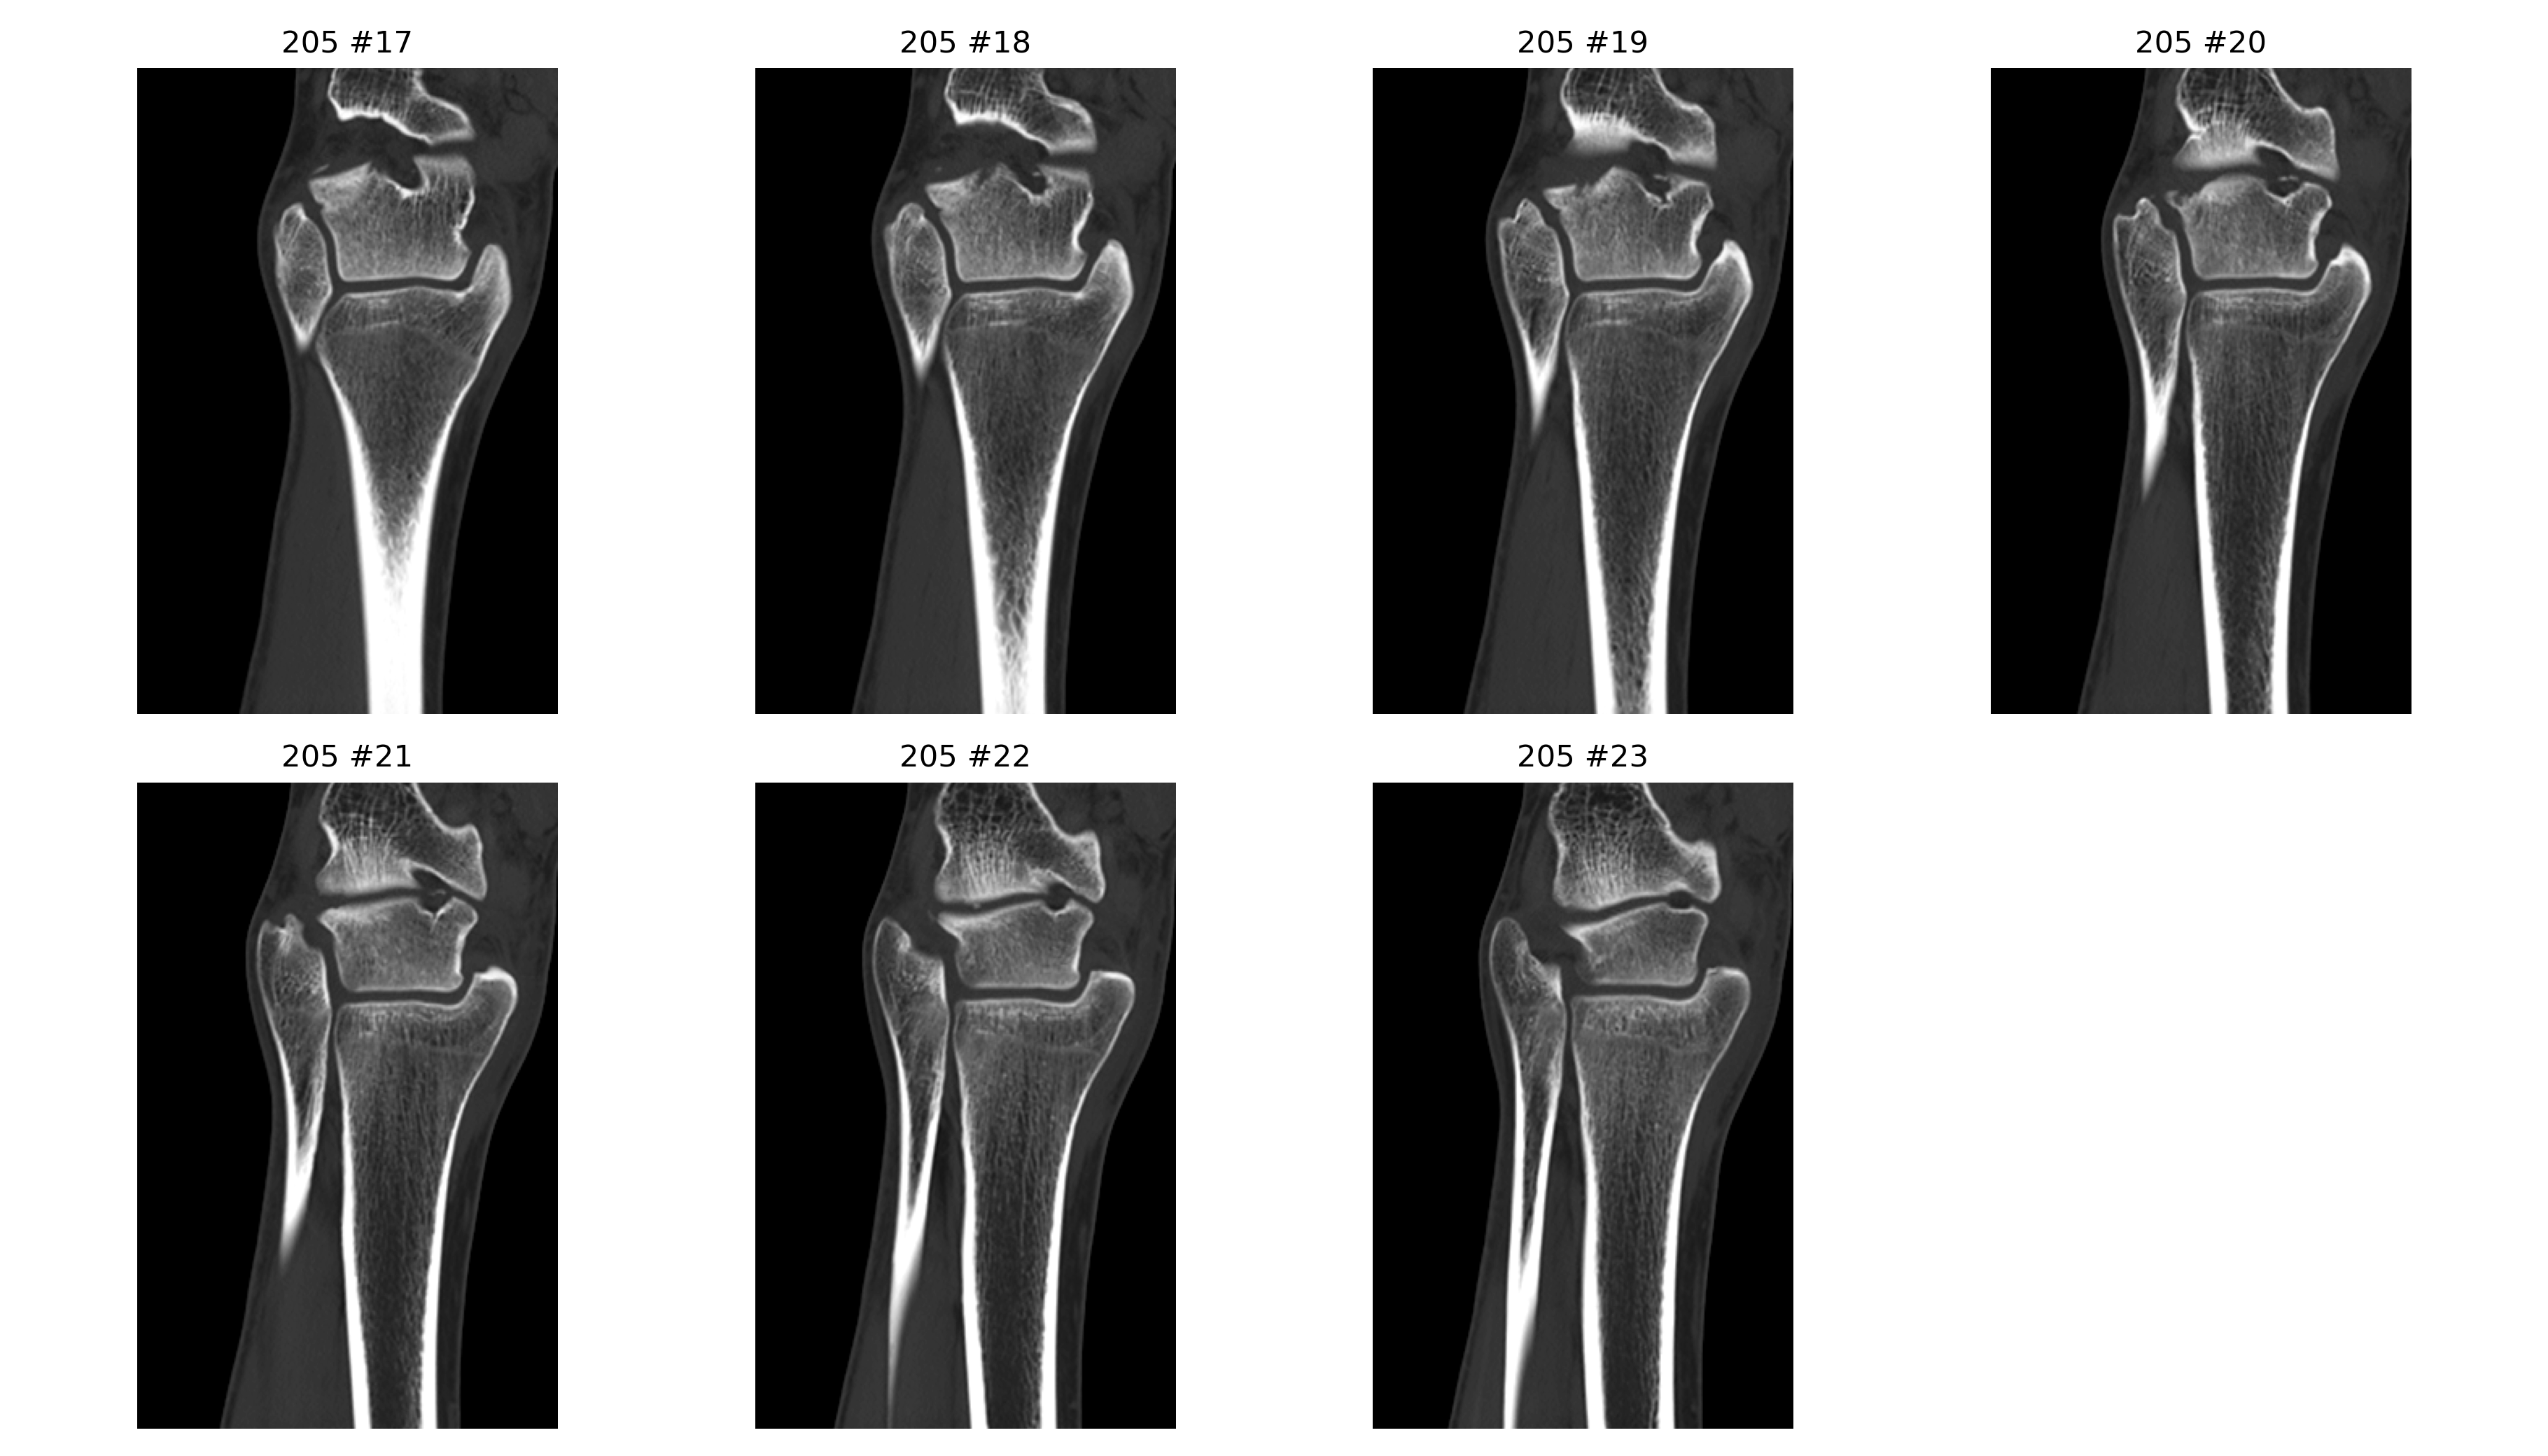

基于 2026-04-02 右踝无对比 CT 原始 DICOM 的辅助分析。核心问题是: 右踝外侧、距骨外侧突及距下关节外侧附近存在高概率关节内骨性损伤, 表现更接近单板滑雪常见的 snowboarder’s fracture。

- 冠状位、矢状位和三维辅助重建里都能反复看到局部骨性不规则和分离感。

三维与关键切面

三维图更适合看骨片和关节面的空间关系;真正判断骨折线、关节面台阶和位移, 仍然要以原始 CT 切面为主。

定量分析与标注图

以下毫米值为近似测量值,作用是帮助沟通位移量级,不等同于医生在工作站上的正式卡尺读数。